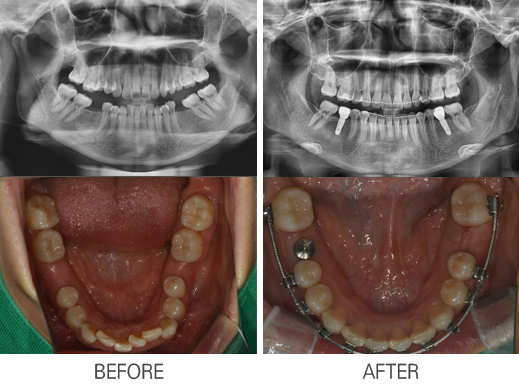

±³Á¤À» µ¿¹ÝÇÑ ÀÓÇöõÆ®

: ±³Á¤À» µ¿¹ÝÇÑ ÀÓÇöõÆ®